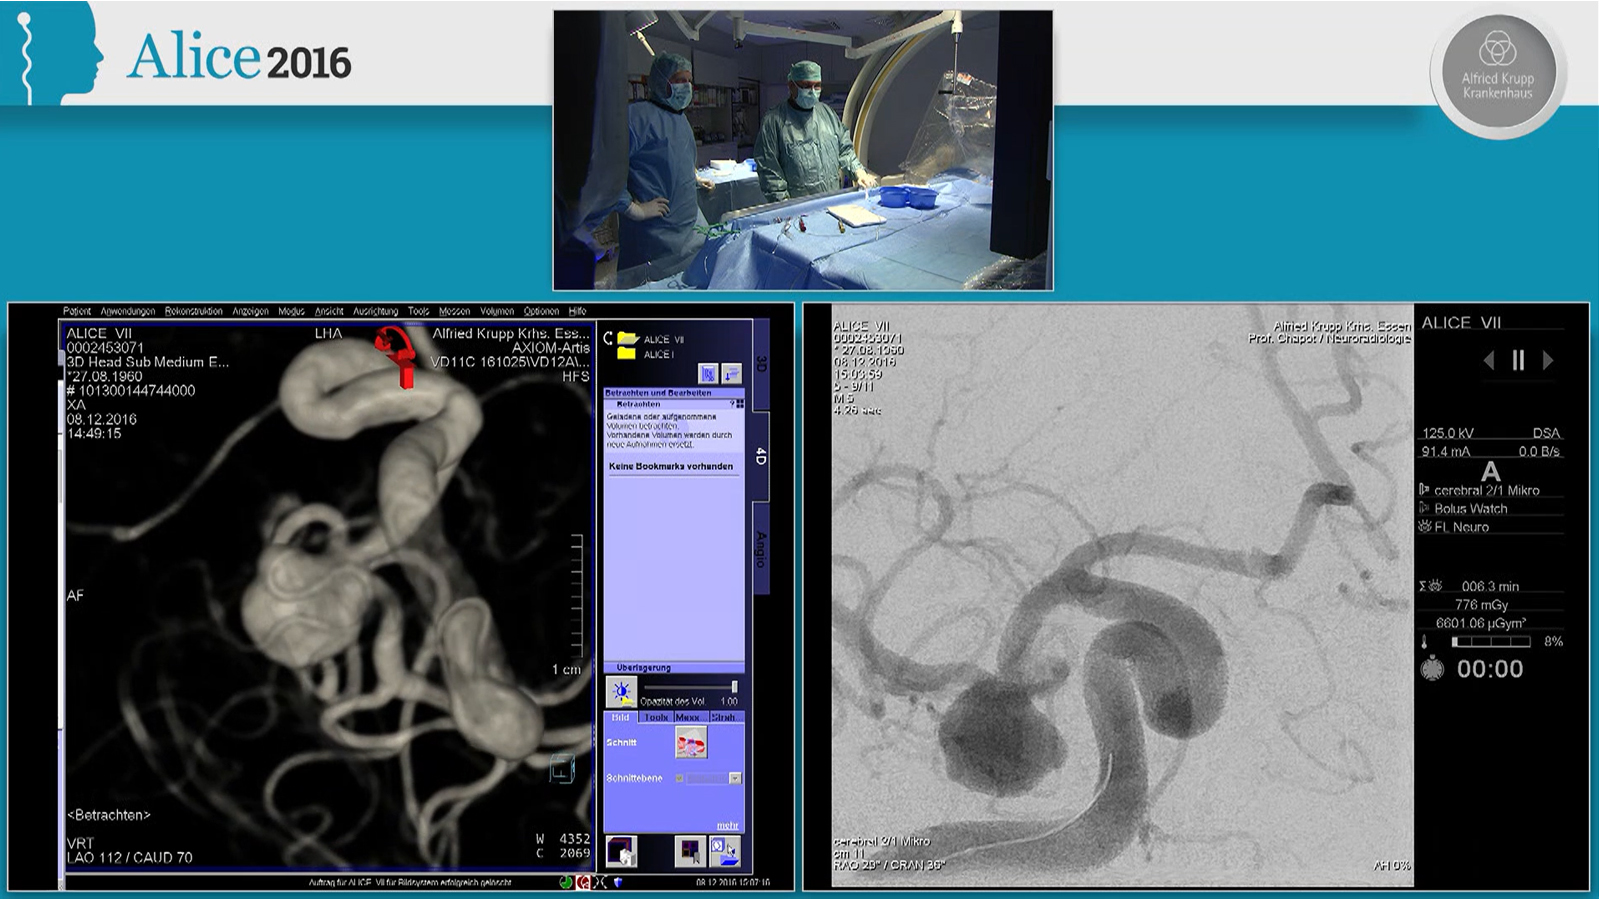

MCA aneurysm treated by double balloon assisted coiling followed by Stenting with Baby Leo

MCA aneurysm treated by double balloon assisted coiling followed by stenting with Baby Leo through Scepter XC